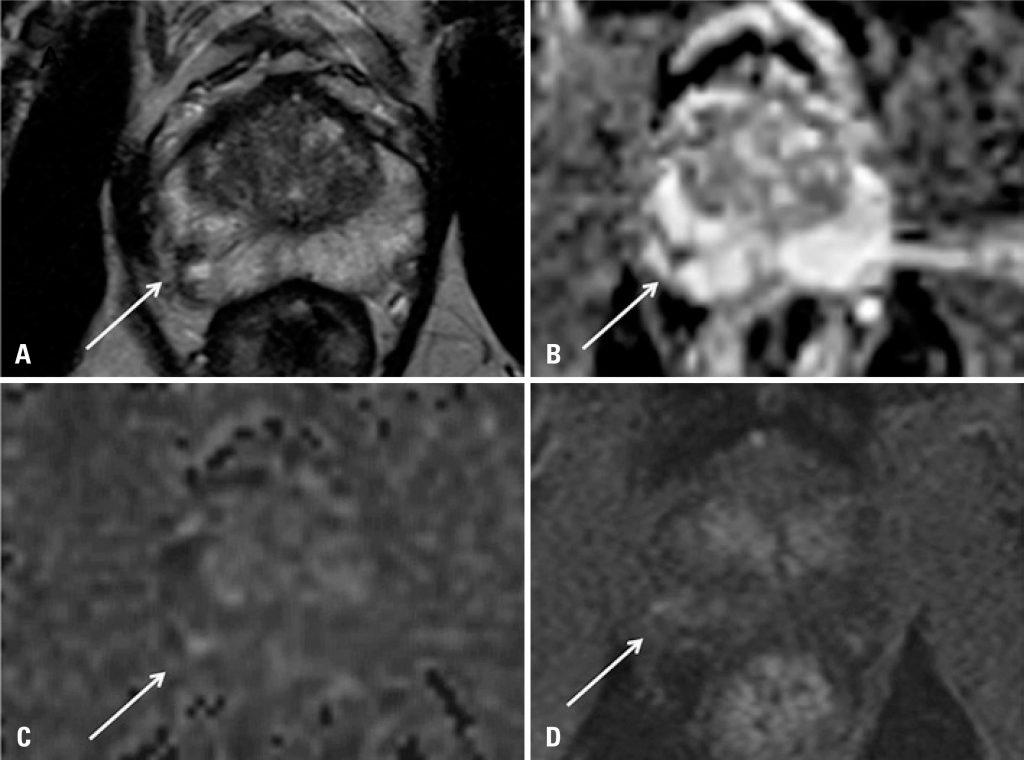

A ressonância magnética de próstata é um método de imagem que tem demonstrado crescente relevância na prática urológica. Devido aos avanços tecnológicos dos equipamentos e à introdução de sequências funcionais, possibilita maior acurácia na detecção e caracterização de tumores prostáticos.